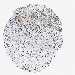

STOMACH CANCER - Protein expressioni

A mouse-over function shows sample information and annotation data. Click on an image to view it in a full screen mode. Samples can be filtered based on level of antibody staining by selecting one or several of the following categories: high, medium, low and not detected. The assay and annotation is described here.

Note that samples used for immunohistochemistry by the Human Protein Atlas do not correspond to samples in the TCGA dataset.

Antibody stainingi

Antibody staining in the annotated cell types in the current human tissue is reported as not detected, low, medium, or high, based on conventional immunohistochemistry profiling in selected tissues. This score is based on the combination of the staining intensity and fraction of stained cells.

Each image is clickable and will lead to virtual microscopy that enables deeper exploration of all samples and also displays staining intensity scores, fraction scores and subcellular localization as well as patient and tissue information for each sample.

HPA040067

HPA061280

CAB005197

CAB016392

CAB079968

Adenocarcinoma, NOS

Adenocarcinoma, High grade